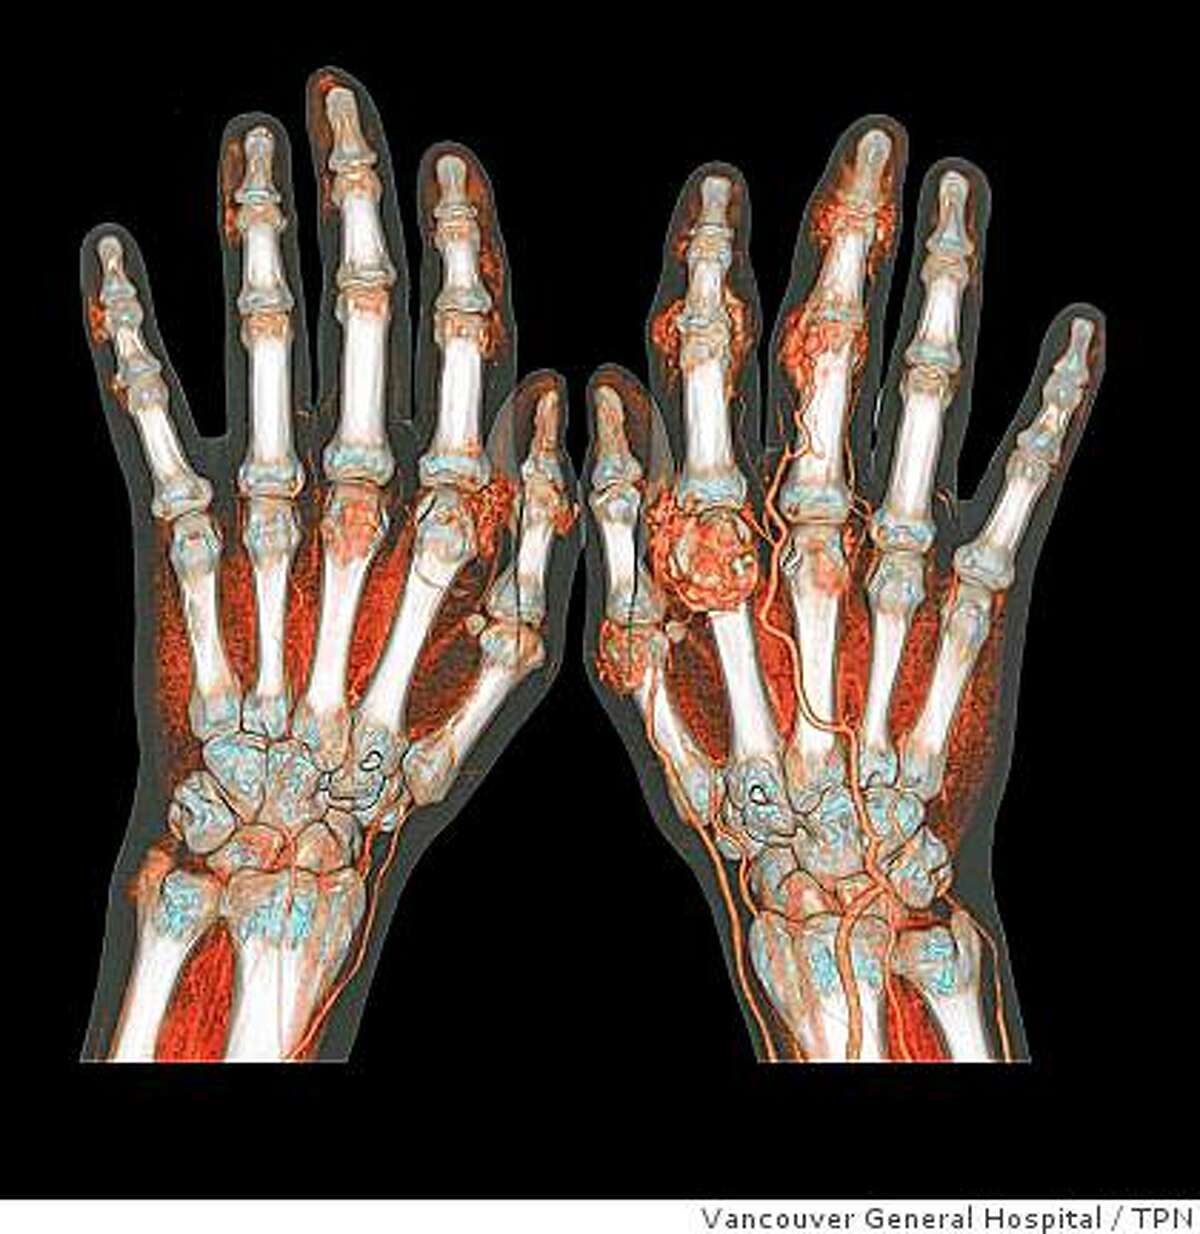

CTscan Reconstruction of the hand DocCheck

CTscan Reconstruction of the hand DocCheck Is It Dangerous To Scan Your Hand in summary, a man is concerned about the potential harm of scanning his hand with a strong light. during the scan, you may feel your body temperature increase and you may experience tingling in your hands and feet. The mri magnet is always on. They are classed as a carcinogen. Magnetic resonance imaging, or m.r.i., is considered one. Is It Dangerous To Scan Your Hand.

CTscan Reconstruction of the hand DocCheck Is It Dangerous To Scan Your Hand curious what will happen if you scan your hand in scanner? during the scan, you may feel your body temperature increase and you may experience tingling in your hands and feet. passing through an airport security portal does not pose a risk to a pregnant woman or her unborn child. They are classed as a carcinogen. Magnetic. Is It Dangerous To Scan Your Hand.